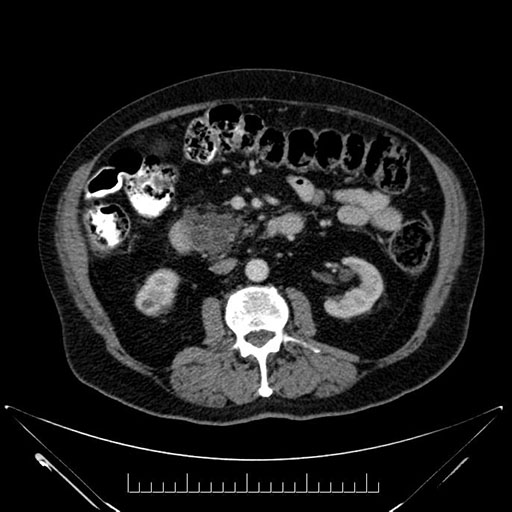

Imaging Analysis

Look through the patient's CT scan to identify any areas of concern for the necessary procedure.

Based on your CT findings, which issue(s) would give reason for "planned slowing down moment(s)" in this case?

Considering a standard Whipple procedure, what step(s) of the operation would you do differently in this case?